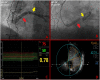

Case summary: We present a case of stable exertional angina due to very-late stenosis of the coronary prosthetic conduit, successfully treated with trans-femoral percutaneous angioplasty and off-label implantation of a balloon-expandable bare-metal stent designed for peripheral artery disease. The multimodality imaging approach gave an essential contribution both to the assessment of the lesion and to the procedural planning. Despite the concerns about long-term results, a peripheral bare-metal stent was preferred over a standard coronary drug-eluting stent due to the remarkable dimension of the Cabrol conduit. Three years after the procedure, the patient is free from angina, and coronary computed tomography showed no significative luminal loss of the stent.